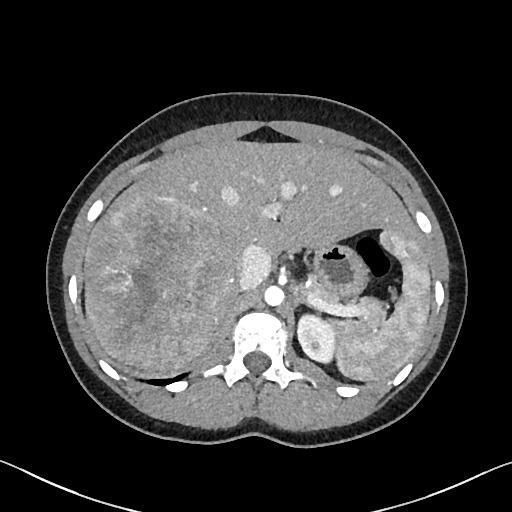

15 yo f presented to ED w/acute onset of RLQ abd pain. CT scan revealed an incidental 14 cm heterogenous mass in the right lobe of the liver. Case by Caroline Bsirini MD, Karen Vanderbilt BS, Lee Ann Hellman PA (ASCP), Michael G. Drage MD, PhD, #Liverpath https://t.co/NSd6y4drwk